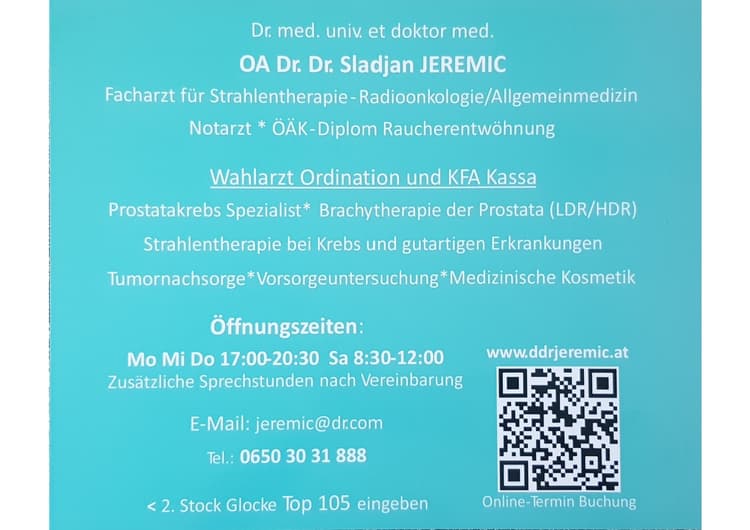

Get Prostate cancer consultation in 3 simple steps

Send Your Request

Submit your non-binding inquiry to the service provider.